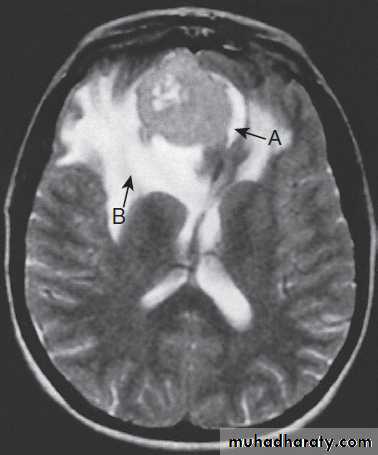

Different techniques of imaging the cervical spine. A Lateral X-ray showing bilateral C6/7 facet dislocation. B Myelogram showing

widening of cervical cord due to astrocytoma (arrows). C MRI showing posterior epidural compression from adenocarcinomatous metastasis to the posterior arch of T1 (arrows).